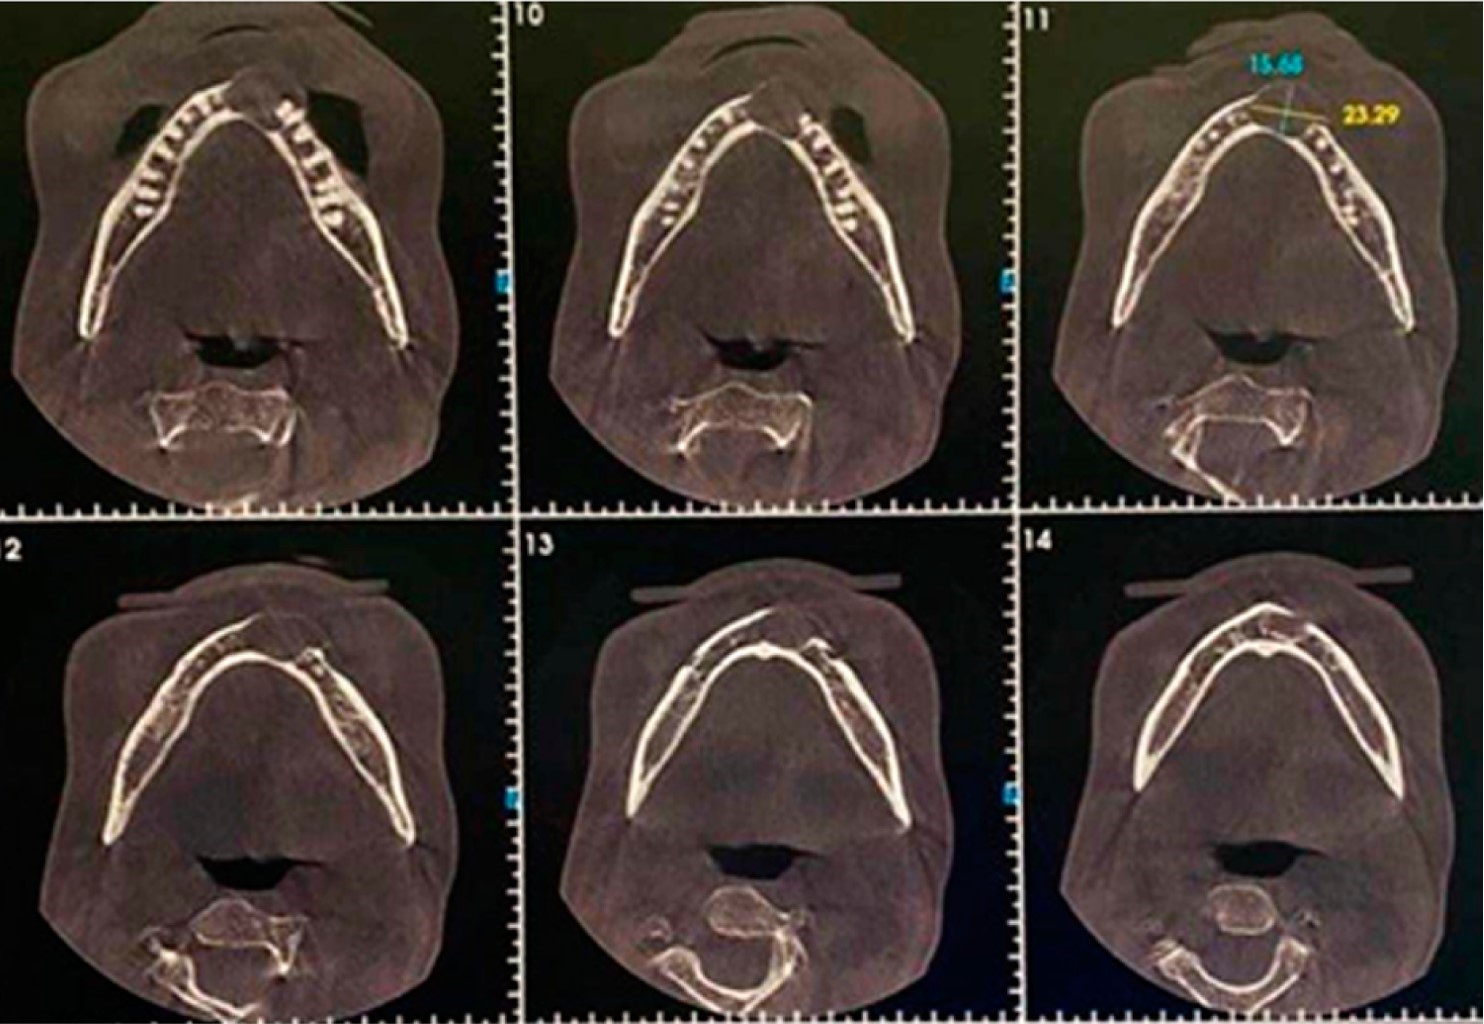

Se solicitó una tomografía computarizada de la cara, en la que se presentó una lesión hiperdensa unilocular de extensión entre los dientes 34 a 42 de halo hipodenso, con bordes definidos, causando divergencia y reabsorción radicular. La lesión con característica quística presentaba 15.68 mm x 23.29 mm de extensión, con expansión de la cortical bucal (Figura 2).